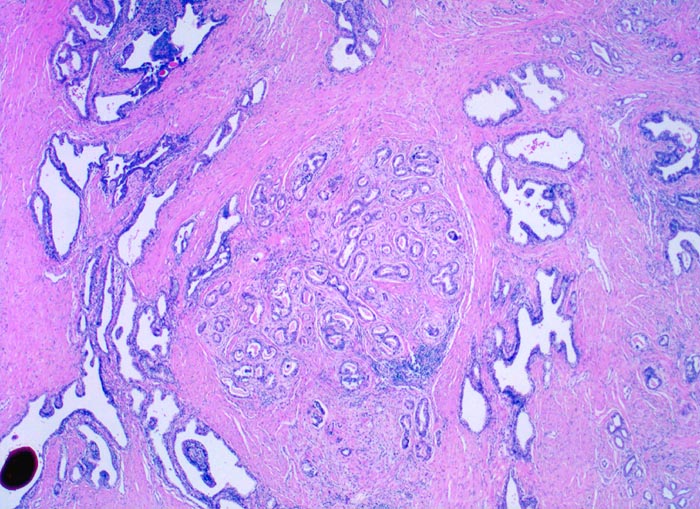

• Normale Prostatadrüsen mit grossen Lumina angeordnet in Läppchen. Das Epithel bildet Falten und besteht aus einer inneren hochprismatischen sekretorischen Zellschicht und einer äusseren Schicht flacher Myoepithelien.

• Herde kleiner Karzinomdrüsen ohne Basalzellschicht.

• Fehlende lobuläre Anordnung der Karzinomdrüsen.

• Konfluierende Drüsen bilden kribriforme Muster.

• Wenig differenzierte Karzinomanteile ohne erkennbare Drüsenbildung.

• Unterhalb der Samenblase sind von flachem Endothel ausgekleidete Lymphgefässe mit Karzinominfiltraten erkennbar (Lymphangiosis carcinomatosa).